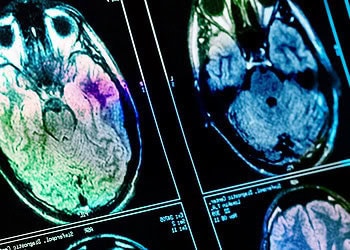

A recent study published in Molecular Psychiatry provides evidence that exposure to cannabis during pregnancy may alter the trajectory of brain development in offspring from the fetal stage through adulthood. The findings indicate that high concentrations of the drug can lead to sustained reductions in brain volume and anxiety-like behaviors, particularly in females. This research utilizes advanced imaging techniques in mice to track these developmental changes over time.

To observe brain development, the scientists used magnetic resonance imaging, or MRI. They scanned the offspring at multiple time points to create a longitudinal dataset. The first set of images came from embryos extracted on gestational day 17. A second cohort of pups underwent scanning on alternate days from postnatal day 3 to 10. A third group was imaged during adolescence and adulthood, specifically on postnatal days 25, 35, 60, and 90. This approach allowed the team to track the growth curves of individual subjects throughout their lives.

Analysis of the embryonic images revealed that exposure to the drug affected physical development in the womb. Embryos exposed to THC had smaller overall body volumes compared to the control group. Despite the smaller body size, their brains showed enlargement in specific areas. The lateral ventricles, which are fluid-filled cavities within the brain, were significantly larger in the THC-exposed group. The corpus callosum, a bundle of nerve fibers connecting the brain’s hemispheres, also appeared larger at this stage.

As the mice entered the neonatal period, the pattern of growth shifted. The THC-exposed pups experienced a period of “catch-up” growth regarding their body weight. However, their brain development followed a different path. The rate of brain growth decelerated compared to the unexposed mice. This slowing of growth affected multiple regions, including the hippocampus, amygdala, and striatum.

By the time the animals reached adulthood, the structural differences remained evident. The reduction in brain volume persisted in regions such as the hippocampus and the hypothalamus. The data indicated a sex-dependent effect in the long-term outcomes. Female mice exposed to THC tended to show more pronounced volume reductions in adulthood compared to males. While male mice did exhibit some volume loss, they showed less severe reductions in specific areas like the cerebellum and olfactory bulbs compared to females.

“In short, we found that exposure to a high concentration of THC early in pregnancy can affect the brain until adulthood,” Cupo explained. “Specifically, we found larger volume of the ventricles, or fluid-filled cavities within the brain, before birth. Then, as the baby mice aged over the first two weeks of life, the brain of THC-exposed pups showed a decreased growth rate compared to the unexposed controls. This smaller volume was sustained until adulthood, especially in female mice.”